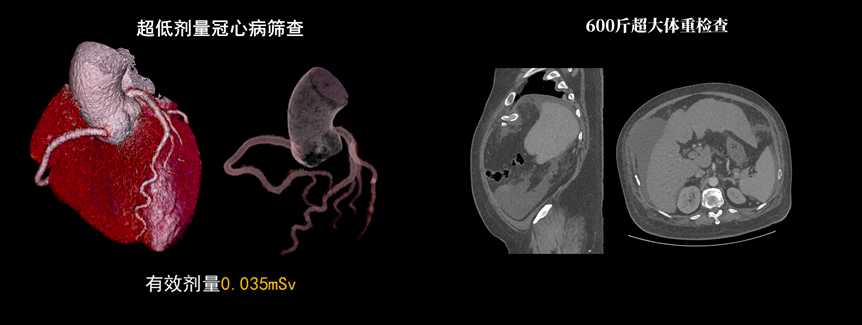

該設(shè)備除具備普通CT的功能外,還具備速度快、精度高、智能化、高效能、微劑量、大孔徑等優(yōu)勢。16厘米Z軸探測器、23毫秒時間分辨率,聯(lián)影天河640CT讓冠脈CTA檢查擁有“不選擇”的權(quán)利。搭載的一站式聯(lián)合掃描技術(shù),輔以便捷高效的后處理功能,AI精準血管分割,自動預(yù)處理加載,逐支血管觀察,全時提效,可實現(xiàn)一次注射造影劑獲取多部位CTA、CTP和4D動態(tài)圖像,不僅可以助力腦卒中解決方案,還可助力腦血管畸形、腦動脈瘤等其他腦血管病的結(jié)構(gòu)和功能評估。

液態(tài)金屬軸承球管,陽極直冷技術(shù),提供30MHU球管熱容量,可高通量連續(xù)掃描。AI劑量調(diào)制、迭代重建等復(fù)合劑量控制方案,為體檢患者提供優(yōu)化劑量掃查。82cm大孔徑,讓大體型患者檢查更加舒適。

天河640CT的寬體探測器單圈掃描即可覆蓋全心臟,搭配快速機架轉(zhuǎn)速和獨家AI冠脈追焦技術(shù),可實現(xiàn)單心動周期內(nèi)無限心率、無限心律的冠脈成像,對于嚴重心律不齊、房顫、房撲,超高心率等情況,天河640CT都能在單心動周期內(nèi)獲得優(yōu)質(zhì)圖像。